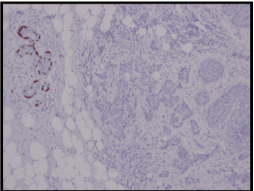

She underwent a left breast wide local excision and a sentinel node biopsy uneventfully in July 2016. The final pathology report was a Grade 3 Invasive Ductal Carcinoma (Slide 1), which was 1.5cm with clear margins. Three sentinel nodes were clear of metastases. Estrogen receptors (Slide 2) and progesterone receptors (Slide 3) were negative. Her-2 was positive. Ki67 was at 60%, which is high.

Slide 1. High Grade Invasive Ductal Carcinoma – primary breast tumour.

Slide 2. Estrogen receptor negative – primary breast tumour.

Slide 3. Progesterone receptor negative – primary breast tumour.